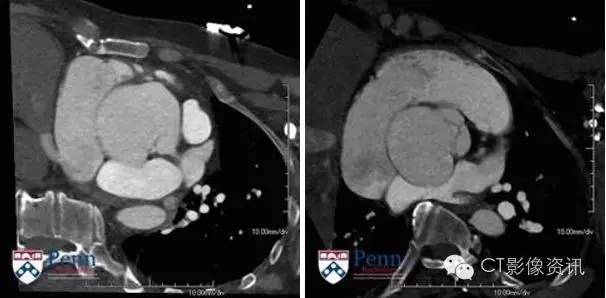

病史 53岁,男性,有心脏杂音及异常超声心动史。为了进一步评估遂转入CT室行CT血管造影。

冠脉CT图像如下

3.异常的位置是在?(单选) 窦管交界处 右冠状动脉窦 左冠状动脉窦 无冠状动脉窦

4.患者出现的心脏瓣膜杂音最有可能与下列何种原因有关?(单选) 主动脉瓣狭窄 主动脉瓣关闭不全 二尖瓣狭窄 二尖瓣关闭不全

5.当患者出现下列何种情况时需进行手术治疗?(单选) 冠状动脉轻度压迫无心肌缺血 尺寸大于3厘米 出现心律失常 轻度主动脉瓣关闭不全